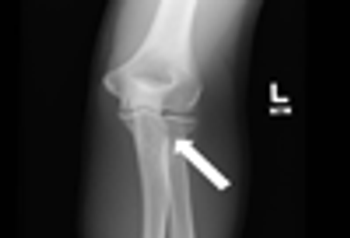

FOOSH Injury of the ElbowBySean Sims, PA-C,Curtis Grenoble, PA-CAugust 17th 2012FOOSH injuries associated with acute onset of pain at the elbow suggest fracture of the radial head, proximal ulna, or humeral condyle or soft tissue injury.